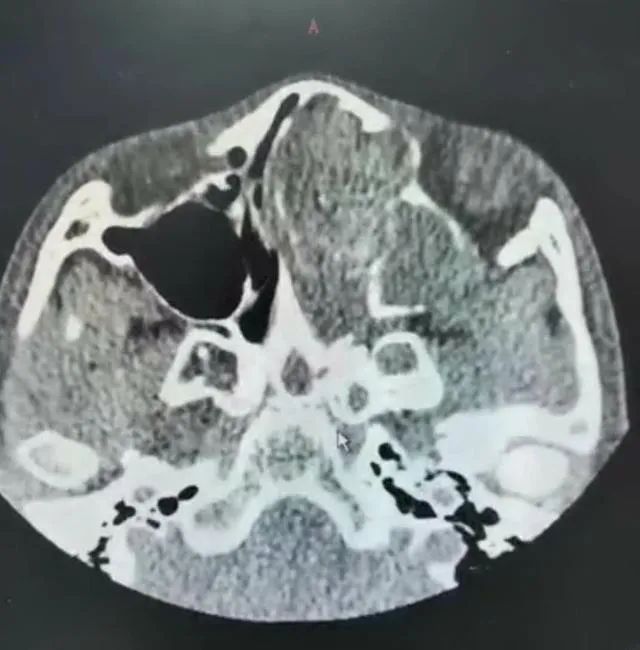

我举起CT片子一看,真把我吓了一跳!片子里左侧鼻腔、鼻窦里满是软组织肿物,正常结构都看不清了,鼻中隔也被压迫的严重右偏,而且肿物已将眼球向外推移!这么重的鼻息肉在儿童里太少见了!

“你看,和右眼相比,这左眼有点向外突起,左边的鼻梁也比右边高一些。”我用手分别捂住孩子的左眼和右眼,差别一下就显现出来了。